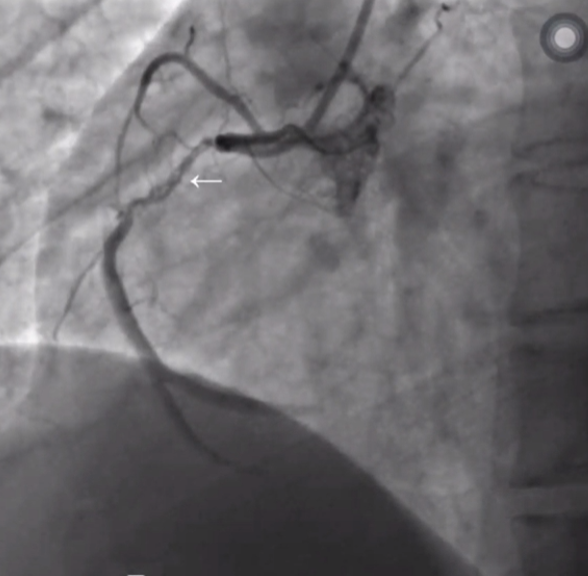

逆向造影显示闭塞远端显影良好 - 易成功

闭塞的右冠发自左冠,侧支循环良好 - 易成功

LAD闭塞侧支循环良好 - 易成功